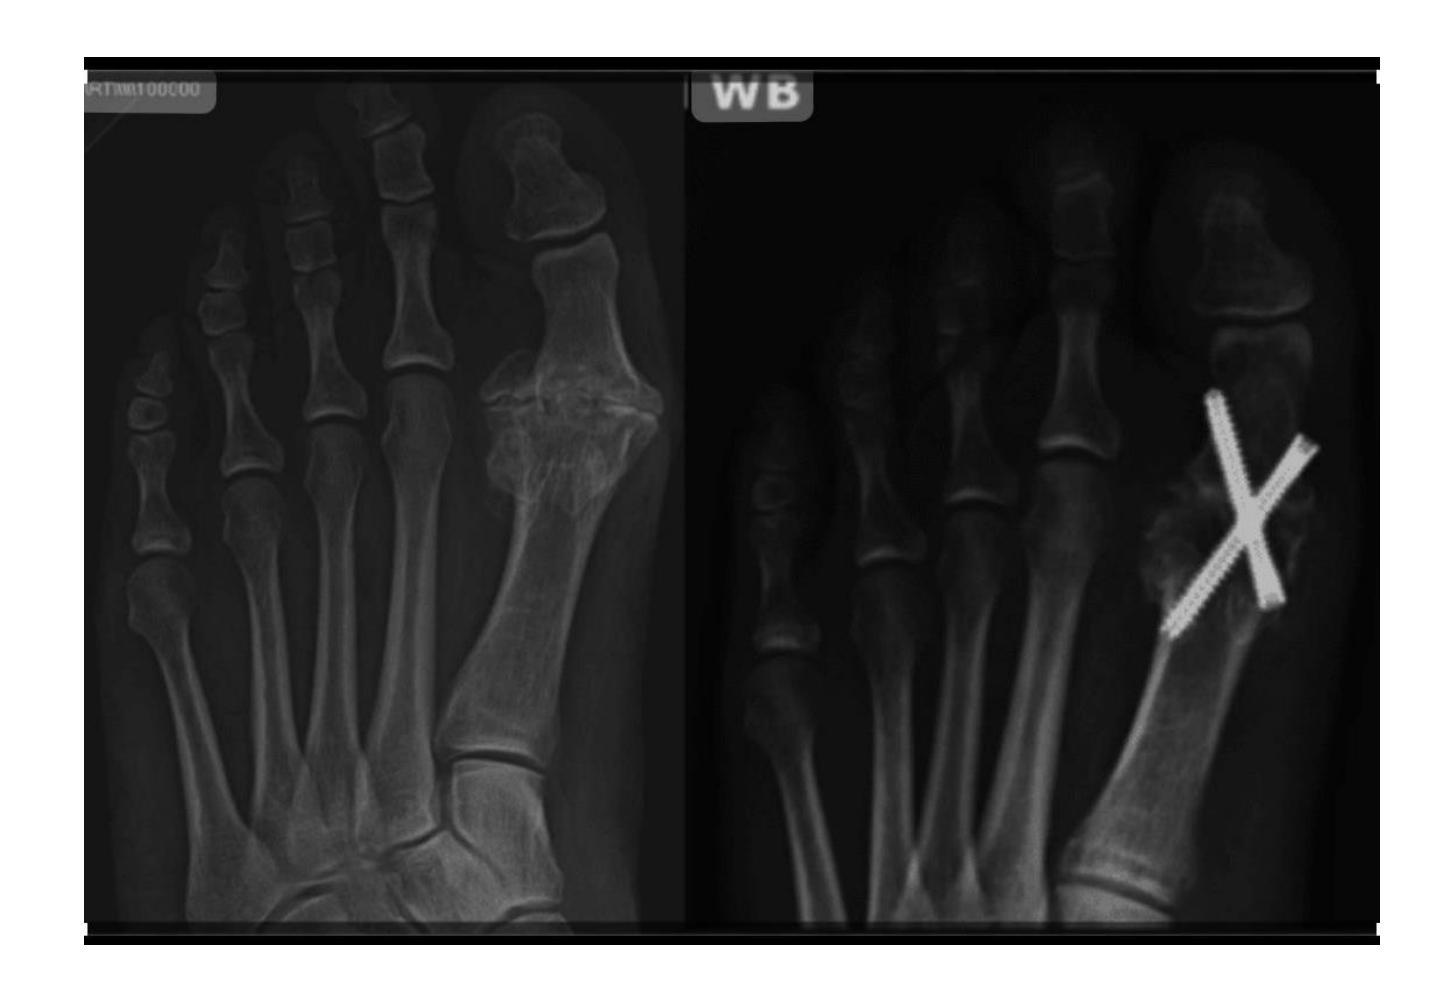

A 17-year-old male had a high ankle sprain followed by pain in his leg. X-ray films were obtained. According to the attached X-ray, which structure has been injured?

- B. Syndesmosis ligament

A 23-year-old male injured his ankle after a twisting ankle injury 2 days back. What is the most likely pathology based on shown x-ray?

Management Question: What is the management of the finding in the image?

- A. Screw fixation for syndesmosis injury

Answer 1: Ankle fracture (Suprasyndesmotic fracture in distal fibula type C with medial malleolus fracture)

Answer 2: ORIF by plate in fibula and syndesmotic screw, and screw for medial malleolus fixation

- 1: Ankle fracture (transyndesmotic fracture in distal fibula type B and medial malleolus fracture)

- 2: Open reduction internal fixation by plate in fibula and syndesmotic screw and screw for medial malleolus fixation